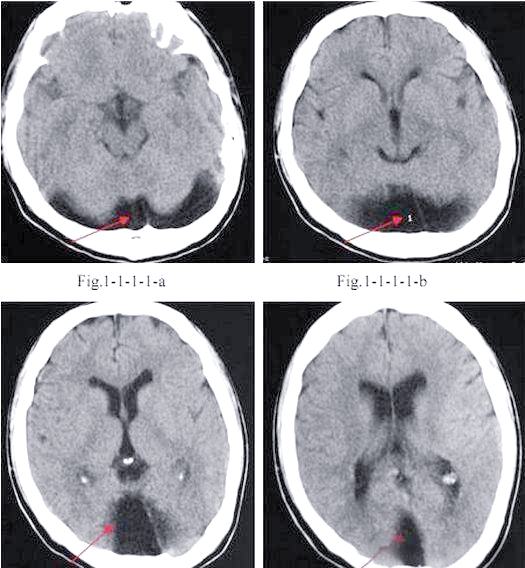

有人写大枕大池,有人说是枕大池蛛网膜囊肿,有依据吗?

大枕大池及其鉴别诊断详解